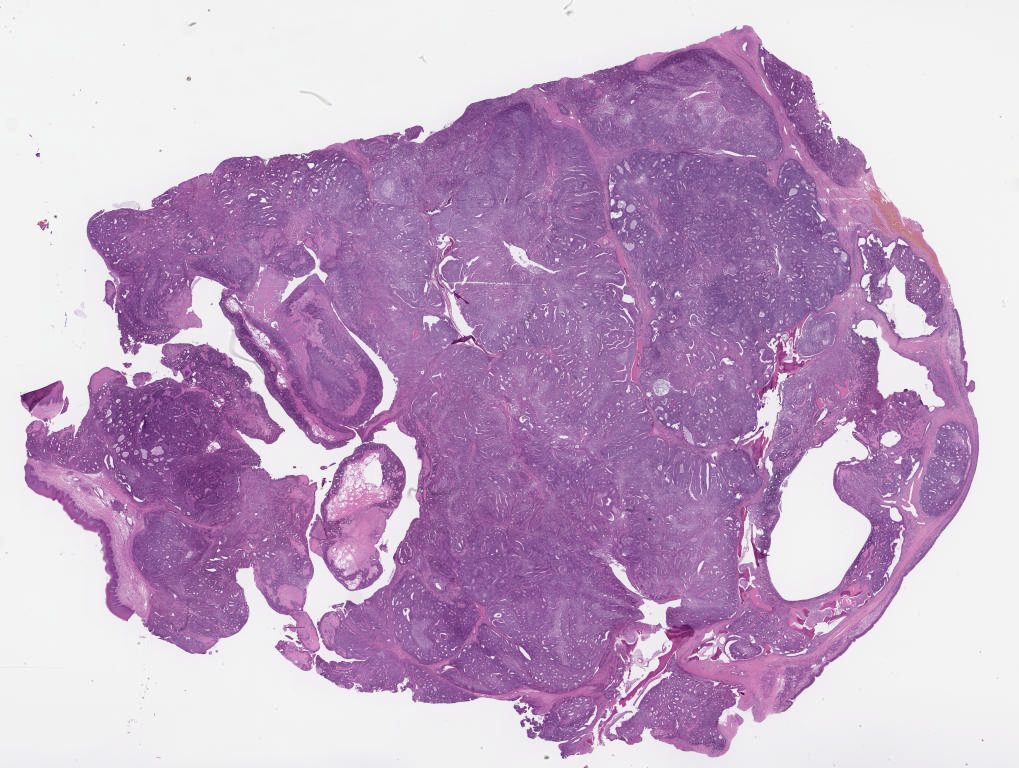

snac1.svs

107568

x

74287

@

40X